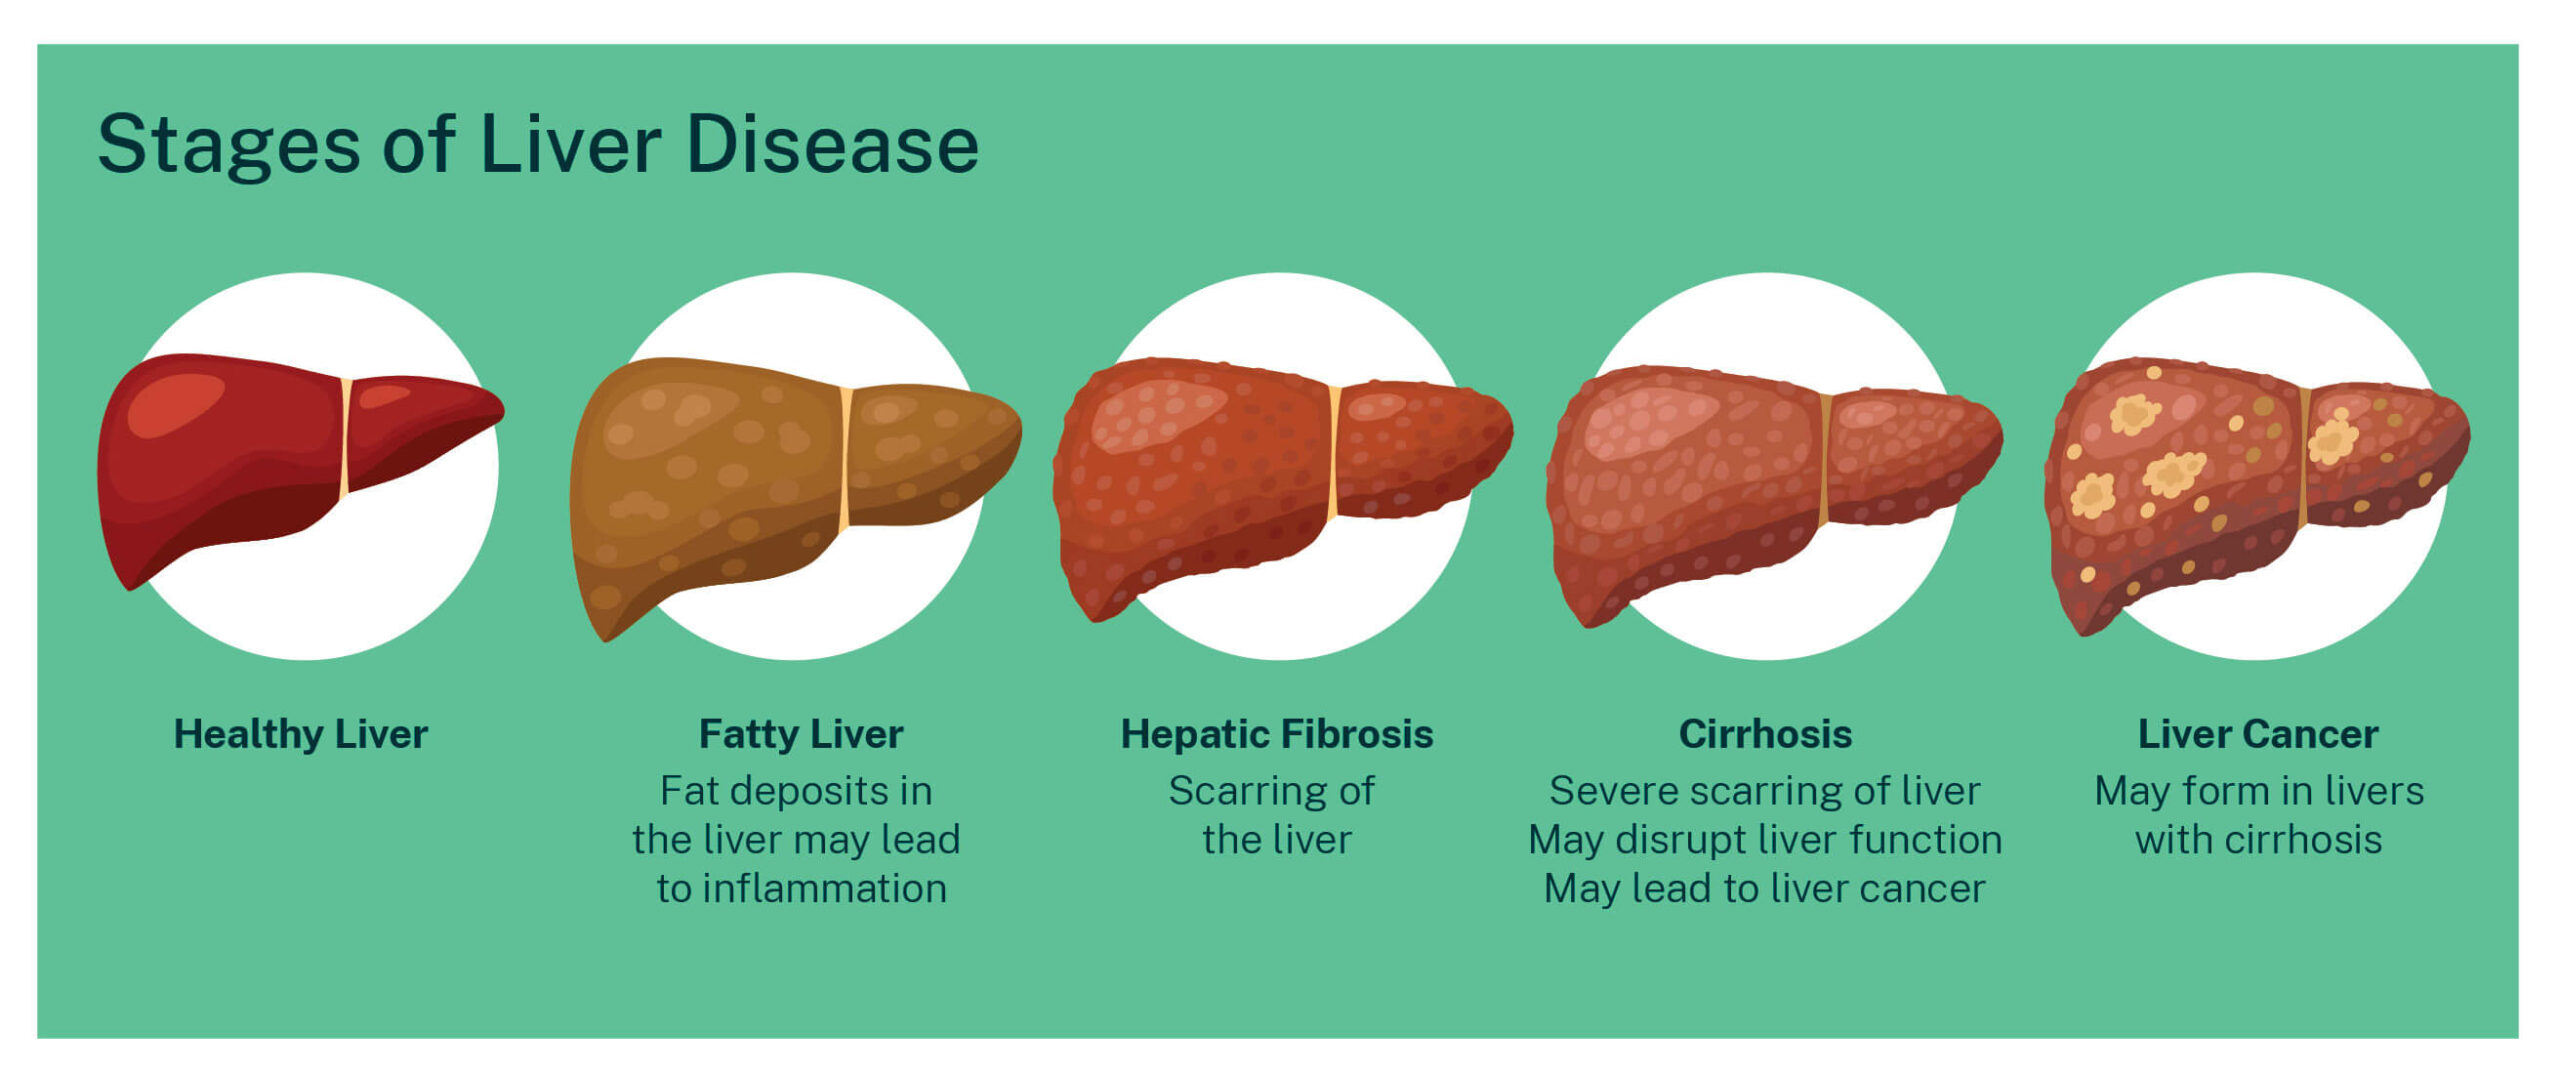

Cirrhosis Of The Liver Symptoms Diagnosis Survival Rate And Treatment

Hepatic Steatosis What Is It Causes Diagnosis Treatment And More